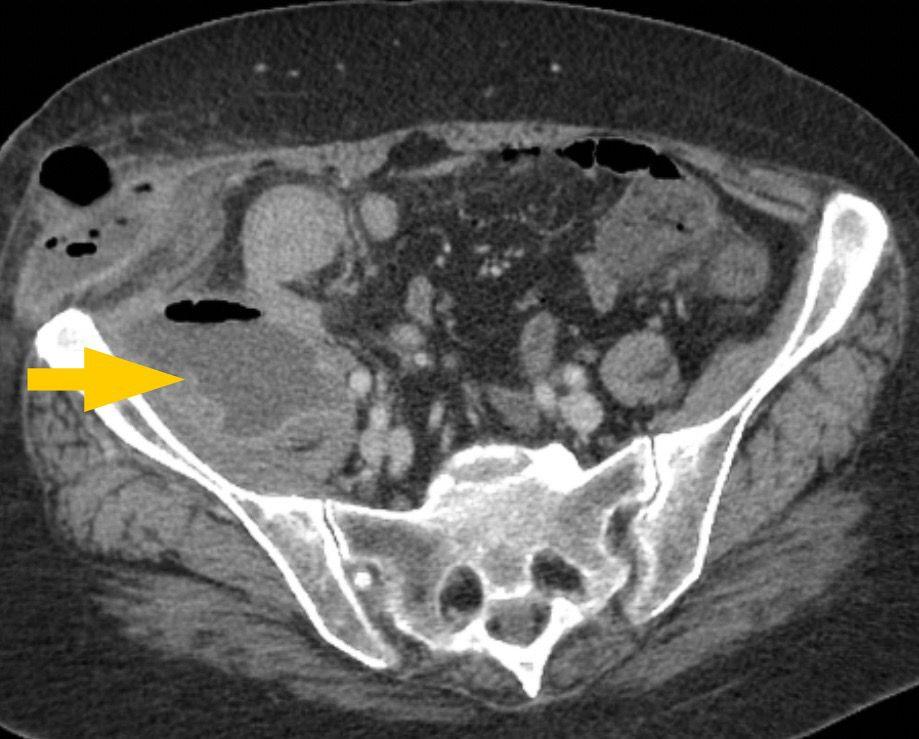

與皮膚膿腫有「紅腫熱痛」這些肉眼可見病徵相比,腰肌膿腫因深入腰椎旁,起初症狀並不明顯。患者通常有發燒、腰痛或腹痛等症狀,痛楚或會放射至髖關節和大腿;而當膿腫沿著肌肉擴展至臗關節附近時,患者腹股溝也會出現腫脹。除了驗血檢查白血球和炎症指數外,最準確的檢查乃是照電腦掃描,並在影像導引下抽取膿來化驗。雖然患者須接受抗生素治療,但膿腫壁卻使白血球、抗體和抗生素這三者,都無法將細菌完全消滅。故此要剿滅這個「三不管」的細菌溫床,必須要介入性治療:首選以創傷性較少的影像導引下經皮引流術來放膿,但面對結構有如城寨房屋般複雜的多房性膿腫,便需要在全身麻醉下做切開引流手術。

腰肌膿腫必須要介入性治療,首選以創傷性較少的影像導引下經皮引流術來放膿。